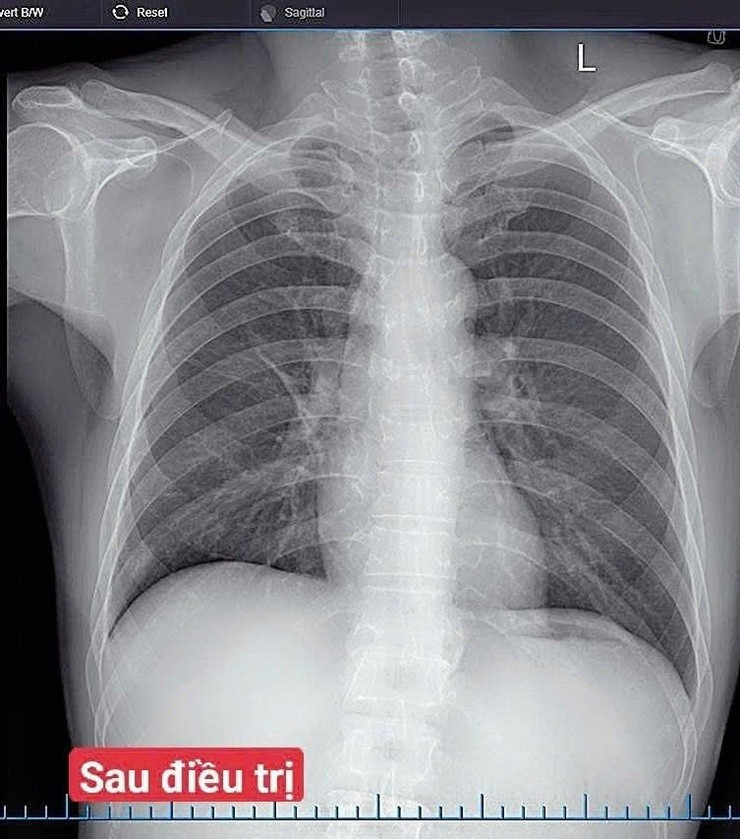

Sau 7 ngày điều trị, tình trạng bệnh nhân cải thiện rõ rệt: Hết sốt, giảm ho, giảm đau ngực, ăn ngủ tốt, chỉ số sinh tồn ổn định.

Hình ảnh sau điều trị của người bệnh. Ảnh BV